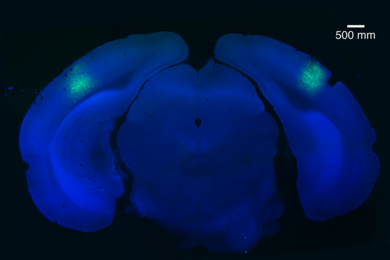

Using light to produce natural sleep patterns

Researchers use optogenetics to trigger REM sleep in mice.